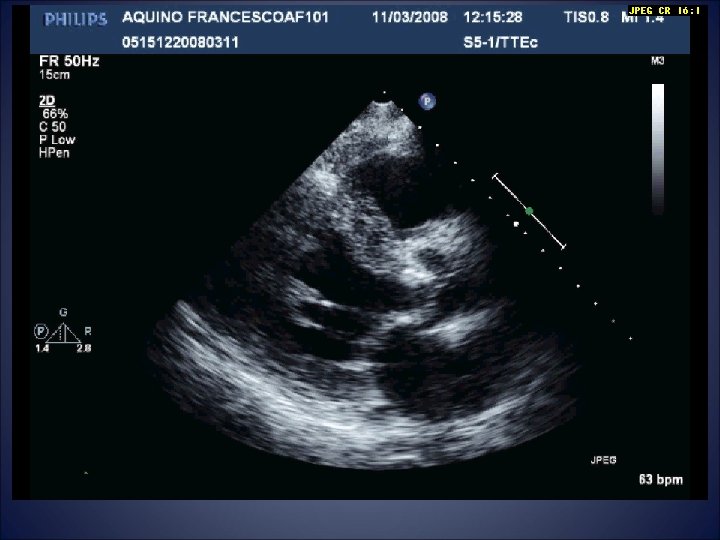

Acute HF hospitalization 13/08/2008 • Raised jugular venous pressure • Pulmonary oedema • Aortic

Acute HF hospitalization 13/08/2008 • Raised jugular venous pressure • Pulmonary oedema • Aortic valve stenosis